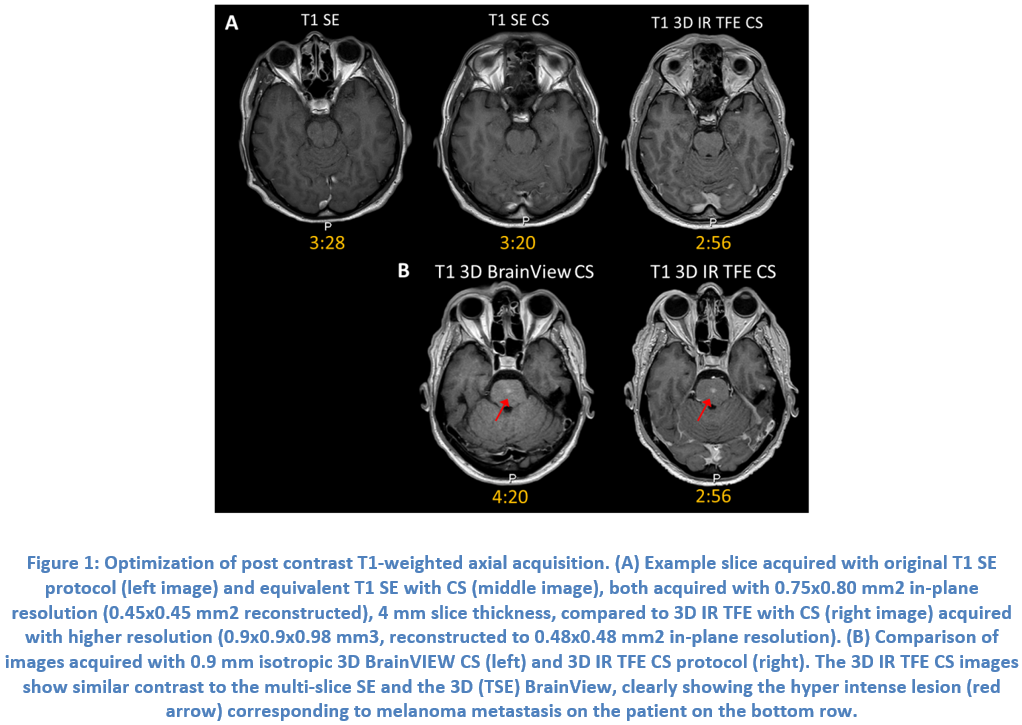

Case Study 2: Compressed SENSE in brain imaging on Philips Ingenia 1.5T (RA5.4)

Dr Rosa Sanchez Panchuelo, University Hospitals Birmingham Foundation Trust